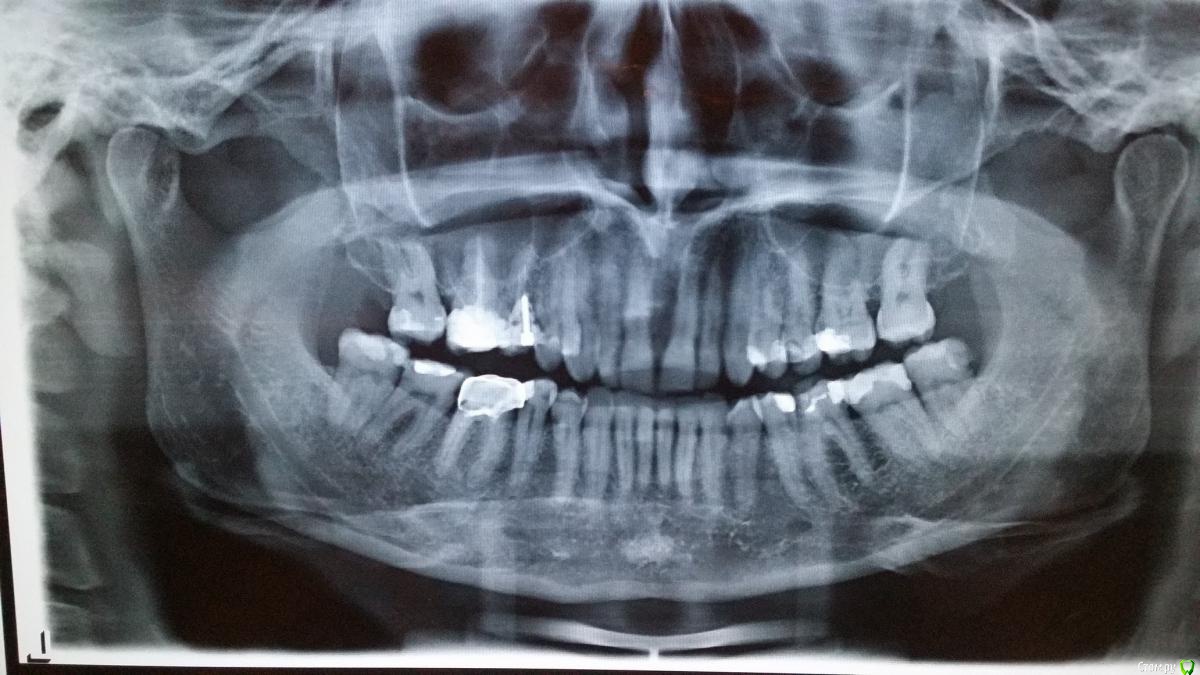

natali777 Опубликовано 6 января, 2016 Автор Поделиться Опубликовано 6 января, 2016 панорамный за месяц до удаления Ссылка на комментарий